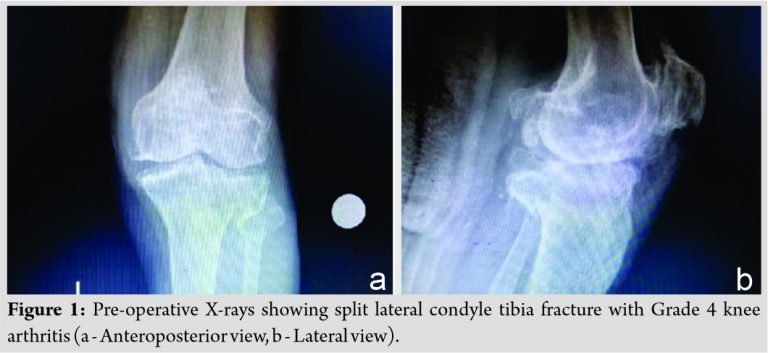

A 76-year-old male patient came to our hospital with complaints of pain, swelling, and difficulty in flexing and weight-bearing in the left knee. The patient had a history of fall from bike 15 days back and took treatment at the local hospital for the same in the form of above knee slab and was referred to our hospital. There was no history of any head, chest, and abdominal injury and the patient was not a known case of hypertension and diabetes. The patient had a history of coronary artery bypass graft surgery 6 years back and is on tablet Ecosprin since then. On local examination, tenderness was present over the lateral tibial condyle, skin condition was good, and range of motion was restricted. X-ray of the left knee was taken, which was suggestive of the left tibia lateral condyle split fracture (Schatzker type 1) with severe osteoarthritis of the left knee (Fig. 1a and b). The patient was managed initially with above knee slab and limb elevation. As the patient was having osteoarthritis with fracture, we planned for primary TKR with stemmed tibial component. Surgery was postponed for 15 days because of patient medical fitness issues.